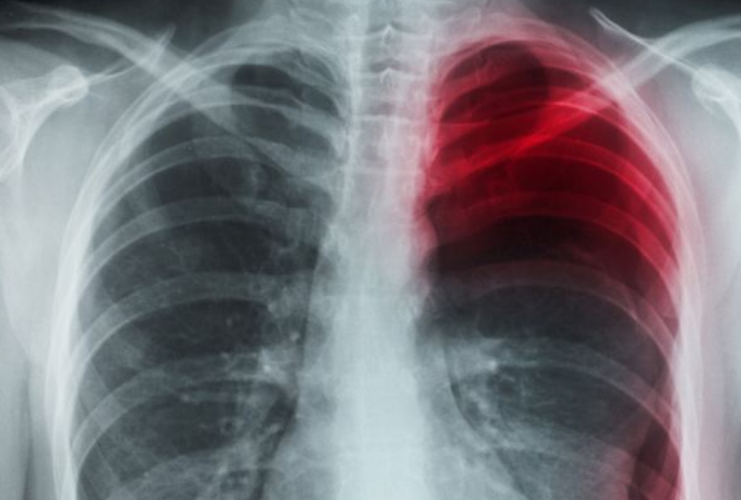

Caz inedit in China. Un barbat, in varsta de 26 de ani, a cascat atat de tare de oboseala incat si-a perforat un plaman.

Barbatul, din provincia Hubei, a povestit presei chineze ca, intr-o dimineata, a cascat si s-a intins atat de violent incat a ajuns la spital cu plamanul perforat, relateaza Daily Mail.

Doctorii au explicat ca de vina pentru accidentul ciudat al barbatului este constitutia acestuia: tanarul e foarte slab si inalt (1.75 inaltime si 57 de kilograme)

Dupa ce s-a trezit si s-a intins, au inceput durerile, asa ca barbatul a ajuns la spital pentru ca de abia putea respira.

Pneumotoracele spontan nu este o afectiune total neobisnuita, explica doctorii, insa in cele mai multe cazuri are loc in urma unei lovituri in piept sau a unei boli a plamanilor. Cele mai comune simptome sunt durerea acuta in piept si dificultatea in a respira.